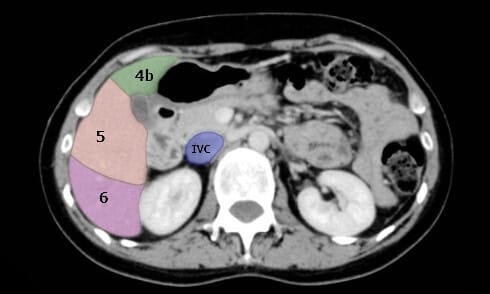

- 문맥 아래쪽은 ‘하부(segment 3, 4b 5, 6 )’로 분류합니다.

- 문맥(portal vein) 하부는 ‘하부(segment 3, 4b 5, 6 )‘로 분류합니다.

- 이제 하나씩 안보이기 시작합니다. 대부분 Segment 3이 가장 먼저 안보이게 됩니다.

- 3 -> 4b – > 5/ 6

- 마지막까지 남는 건 S6 또는 S5/6 경계가 되겠습니다.

- Created by Modifying Hocking J, Liver segments (annotated CT). Case study, Radiopaedia.org (Accessed on 23 Apr 2025) https://doi.org/10.53347/rID-45972